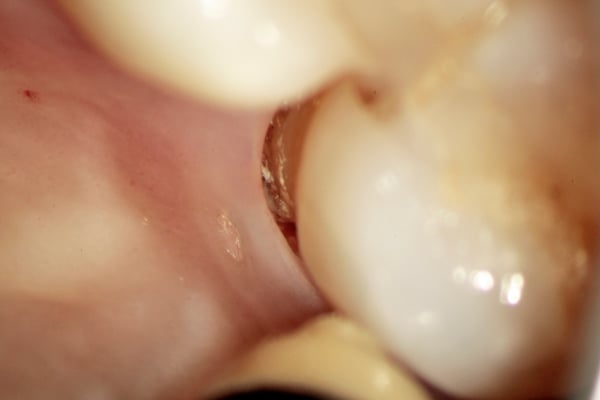

ポケット

肉眼では見えない奥歯の奥の歯と歯肉の境目(ポケット)も中の様子も拡大視野下では診ることが可能な場合があります。